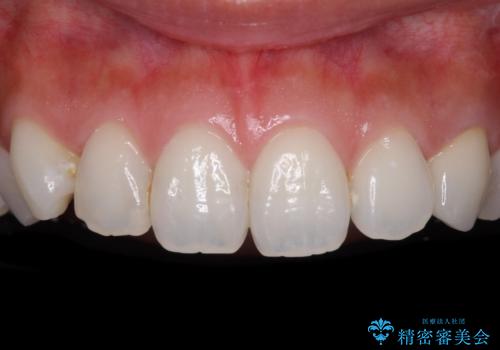

[前歯の変色] 前歯の見た目を改善したい

![[前歯の変色] 前歯の見た目を改善したいの症例 治療後](https://seimitsushinbi.jp/wp/wp-content/uploads/2021/05/1f01d9f0751d14a2f5d20ed7475c6e38-500x350.jpg?v=1622180216)